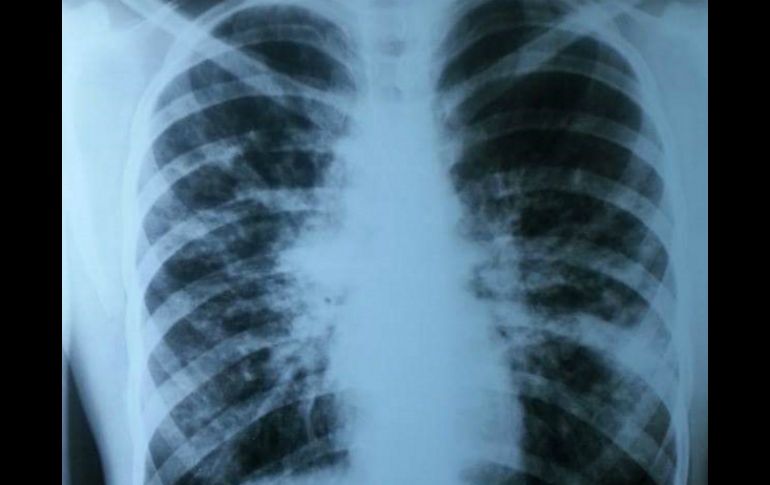

Tecnología | La enfermedad congénita-hereditaria crónica aparece en los primeros meses de vida Diagnóstico tardío de fibrosis quística reduce expectativa de vida La enfermedad congénita-hereditaria crónica y progresiva aparece en los primeros meses de vida Por: NTX 19 de abril de 2016 - 19:10 hs Si no se atiende a tiempo se resta tiempo de vida, ya que la expectativa es de 18 años. NTX / ARCHIVO CIUDAD DE MÉXICO (19/ABR/2016).- Solo 15 por ciento de los menores de edad que tienen fibrosis quística (FQ) son diagnosticados, y muchos de ellos tardan hasta 2.6 años en tener una valoración precisa, lo cual les resta calidad y años de vida, alertaron especialistas. Durante el Foro "Fibrosis quística, su tratamiento y su futuro", realizado en el Senado de la República, dieron a conocer que se trata de una enfermedad congénita-hereditaria crónica y progresiva que afecta a una de cada ocho mil 500 personas. Se estima que cada año se presentan entre 350 y 400 nuevos casos, de los cuales sólo 15 por ciento se diagnostican, mencionó Ricardo Lemus Rangel, especialista del Servicio de Neumología del Hospital General "Dr. Gaudencio González Garza", del Centro Médico Nacional La Raza. Explicó que esta enfermedad aparece en los primeros meses de vida y se caracteriza por tos crónica, respiración agitada, infecciones pulmonares recurrentes y por evacuaciones abundantes, frecuentes, grasosas y de muy mal olor. Uno de los problemas es que frecuentemente se confunde con enfermedad gastrointestinal y no se atiende a tiempo, lo cual resta tiempo de vida a los pacientes ya que la expectativa es de 18 años, pero algunos fallecen antes. "Se requiere de un mayor acceso a centros de atención, a medicamentos innovadores que permitan mejorar la expectativa de vida como en países desarrollados que es de 40 años, y sobre todo que haya un diagnóstico temprano en los primeros días de nacido mediante el tamiz neonatal semiampliado", expuso. Agregó que en promedio el tratamiento tiene un costo anual de 40 mil dólares por paciente con terapias innovadoras, lo cual puede parecer muy alto. Aunque si se toma en cuenta que se reducirían gastos en hospitalizaciones y fármacos que actualmente sólo sirven para aliviar los síntomas y no para controlar la enfermedad, el costo-beneficio es mayor. Guadalupe Campoy Ruy Sánchez, directora de la Asociación Mexicana de Fibrosis Quística, explicó que 95 por ciento de los pacientes diagnosticados con esta enfermedad mueren a causa de problemas pulmonares crónicos, debido a que producen moco anormal que bloquea los conductos respiratorios y propicia infección crónica. Además, la mucosidad afecta la absorción de nutrientes y el paciente sufre desnutrición progresiva. La especialista agregó que se trata de un padecimiento raro o huérfano, por lo que se está buscando que llegue a todo el país el tamiz semiampliado y que cuando haya el diagnóstico los padres de los menores tengan claro cómo y dónde se va a dar atención al paciente. Temas Ciencia médica cáncer de pulmón Enfermedades Calor de hogar Salud general Lee También ¿Cuánto tarda una persona con depresión en llegar al tratamiento? Razones por las que beber agua mineral en exceso afecta tus huesos y dientes ¡Toma nota! 5 razones para lavar los trastes en casa con sal 5 motivos por los que DEBES tener un vaso de agua junto a tu cama al dormir Recibe las últimas noticias en tu e-mail Todo lo que necesitas saber para comenzar tu día Registrarse implica aceptar los Términos y Condiciones